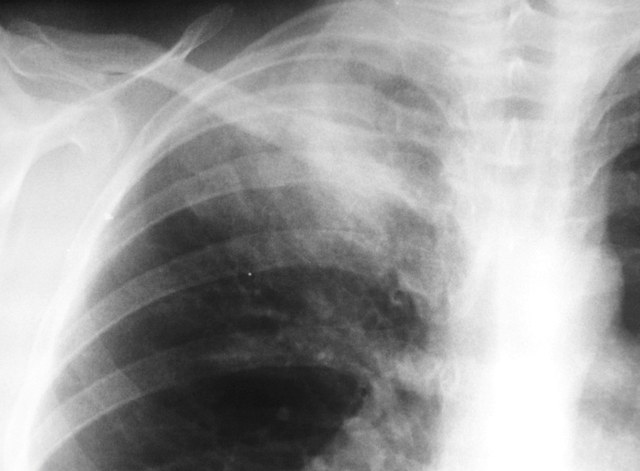

Женщина 32 года; месяц как кашляет. Повышения температутры тела не отмечала. Изначально выполнили рентгенографию. Что делать дальше?

Ок, мы определились с дифференциальным рядом при такой рентгенологической картине (Затемнение верхених сегментов правого лёгкого, S2). Какую рекоммендацию Вы бы дали такому пациенту? Что будем делать дальше?

Далее рекомендуем лабораторные исследования, КТ легких.

KT

Давайте определимся, для начала обозначим какие КТ признаки мы видим на представленных сканах. И главное это не перечисление вариантов диагнозов (если нет однозначного варианта); а определить что надо сделать следующим этапом для достижения окончательного диагноза.

Вполне адекватная тактика. КТ контроль через 3-4 недели после антибактериальной терапии, совершенно правильно.

В данном случае, пульмонолог решил пойти на бронхоскопию; был забор материала. Лабараторный анализ (ПЦР) выявил положительную реакцию на туберкулёз.